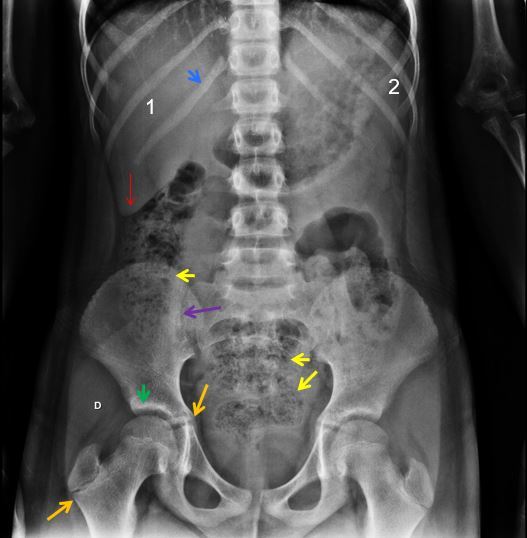

NOME DO EXAME? INCIDÊNCIA? IDENTIFIQUE:

RD SIMPLES DO ABDOME EM DECÚBITO DORSAL.

SETA VERMELHA- ESTÔMAGO

SETA AZUL- CONTORNO DO RIM D

SETA BRANCA – CÓLON TRANSVERSO

SETA VERDE- PSOAS E

SETA NEGRA – FAIXA ADIPOSA LATERAL DO ABDOME ( ESPAÇO PARARRENAL POSTERIOR)

OBSERVE OS PLANOS ADIPOSOS NA CAVIDADE PÉLVICA DELIMITANDO A BEXIGA. ISTO PORQUE TEM TECIDO ADIPOSO CIRCUNDANTE.NUM PACIENTE MAGRO OU EM CRIANÇAS ESTES PLANOS SERIAM INVISÍVEIS.

1- FÍGADO SETA VERMELHA – BORDA HEPÁTICA

2- BAÇO SETA AZUL – 12º ARCO COSTAL D

SETAS AMARELAS – FEZES NO CÓLON ASCENDENTE E RETO E SIGMÓIDE ( MICROBOLHAS GASOSAS)

SETA ROXA- ARTICULAÇÃO SACRO-ILÍACA D

SETA VERDE- ARTICULAÇÃO COXO-FEMORAL DIREITA.

TRATA-SE DE UM ADOLESCENTE PORQUE AS LINHAS DE CRESCIMENTO (SETAS LARANJAS ) SÃO VISÍVEIS.